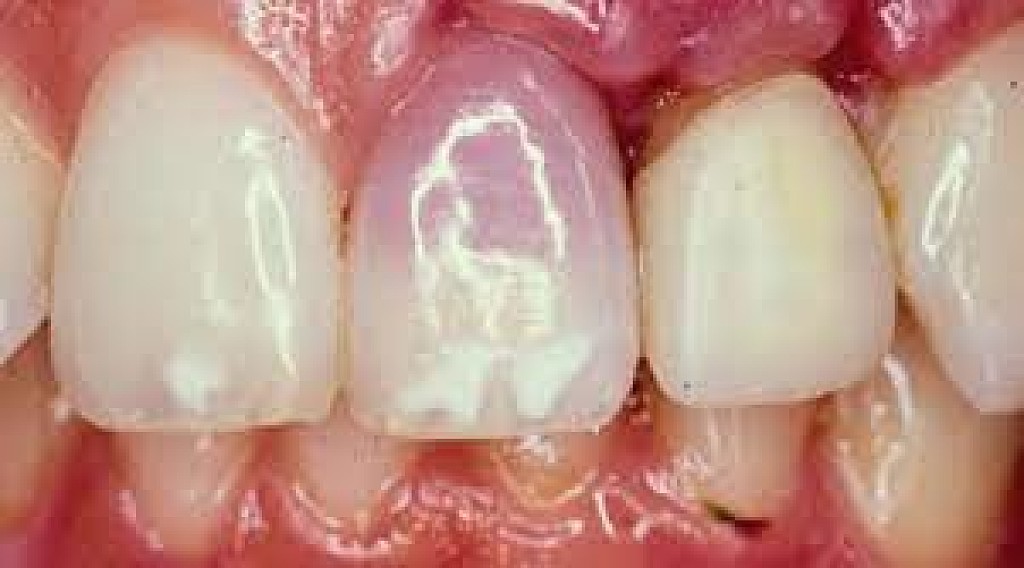

What Causes The Dark Line On My Gums?

You have seen smiles that you know have dental crowns in the front. You look at them and say to yourself that something is not natural. Many times, it is the dark rim of gum tissue that gives it away. The dark rim of gum tissue does not occur around natural teeth, only around teeth that have been covered with dental crowns.

The dark line is associated with an old porcelain dental crown. This style of dental crown is referred to as a porcelain fused-to-metal dental crown because it uses tooth-colored porcelain on the outside and it uses metal under the porcelain for strength. The dark line originates from the edge of the dental crowns where the porcelain and the metal meet at a knife-edge at the gum line. At the knife-edge, a very thin amount of the metal always shows. One of the illusionary techniques cosmetic dentists have used was to hide the thin dark line under the gum line. Over time, the gum tissue would recede and expose the dark line. In some patients the dark line would show through the gum and make it appear dark as well.

How Do You Get Rid of It?

The only way to eliminate the esthetic problem is to replace the dental crowns. When replacing just one single dental crown in the front, you should expect that it might take more than one try-in of the new dental crown before it is permanently cemented into place. Because your central incisors are the most prominent teeth in the mouth, matching them is the most difficult esthetic challenge. Only the best dental technicians are able to mimic one central incisor tooth next to another.

What Are Some of the Replacement Dental Crowns Like?

Some of the clever ways dentists and dental technicians have been able to mimic natural teeth is through the new advancements in dental materials. New all-tooth-colored ceramic dental crowns are the latest technological advancement cosmetic dentists have to recreate natural teeth. In comparison to porcelain fused-to-metal dental crowns, all-ceramic dental crowns do not contain any metal, thus no dark line can appear.